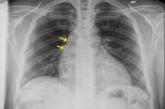

Article20-year-old man • sudden-onset chest pain • worsening pain with cough and exertion • Dx?Author:Rachel M. Coleman, MD, FAAPPublish date: January 21, 2021► Sudden-onset chest pain► Worsening pain with cough and exertion► No improvement with naproxenRead More